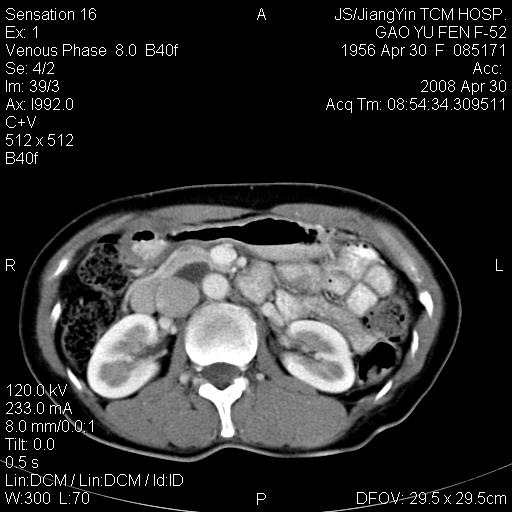

标题: CT13307:肠系膜囊肿? [打印本页]

标题: CT13307:肠系膜囊肿?

囊性淋巴管瘤可能比较大。

良性囊性占位,来源于肠系膜的可能性大

肠系膜囊肿可能

囊性淋巴管瘤?肠系膜囊肿?都有可能!

图像少,不能连续起来看,不太敢确定囊肿前方的条状结构是十二指肠水平段?如果是,那肠系膜囊肿,淋巴管瘤都有可能。

病变位于肾静脉后方,支持腹膜后占位性病变,以囊性淋巴管瘤可能性大.